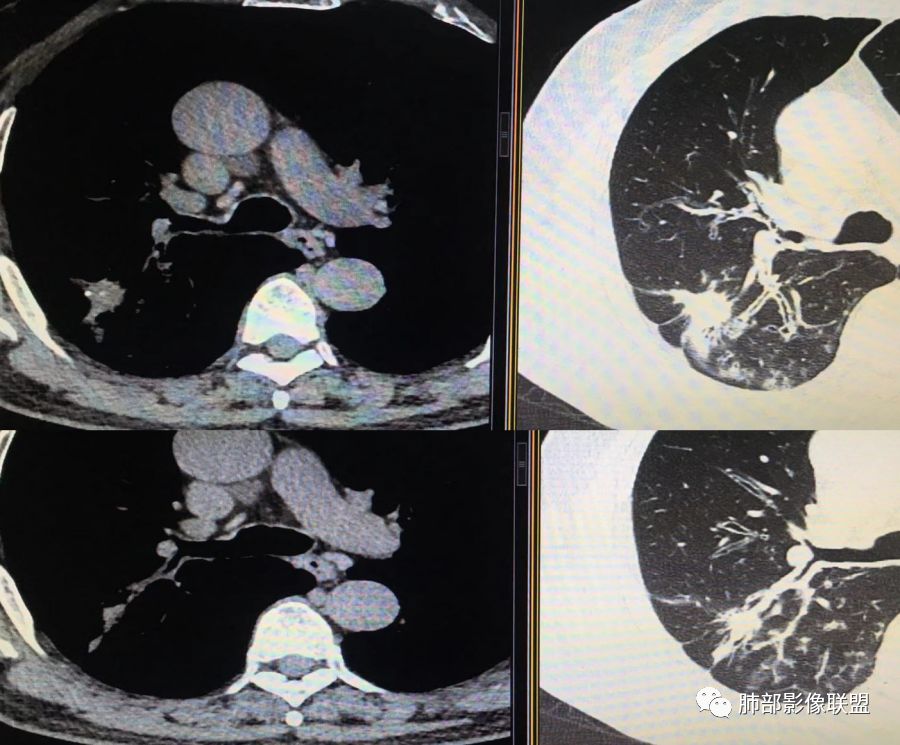

胸CT示病变位于右肺上叶,右肺上叶前段支气管壁不规则增厚狭窄、远端扩张。右肺上叶后段实变影,纵隔窗实变内可见钙化灶,可见支气管引流征,引流支气管壁明显增厚,边缘可见短硬毛刺,胸膜牵拉,u型征,周围可见卫星灶,并可见支气管扩张及其管壁增厚;病灶整体存在膨胀性生长。考虑良性病(结核)变基础上合并癌变,腺癌?

患者中老年男性,咳嗽喘息半年。查体双肺闻及哮鸣音。胸部CT:右肺上叶后段不规则结节灶,可见长毛刺、胸膜牵拉、分叶及钙化征象,周围见点片状卫星灶,近端支气管壁增厚,呈支气管爬行征。综合考虑结核。鉴别恶性病变。

老年男性,咳嗽半年,右肺上叶后段实性结节伴粟粒状卫星灶,结节内有钙化,部分边缘平直,周围见长索条,有胸膜牵拉,结核是明确的,常规需要增强判断有无合并肺癌,当然该患者已经穿刺。

右肺上叶后段结节,点状钙化,边缘见细长毛刺,胸膜凹陷,卫星灶伴树芽症,支气管壁增厚扩张,有截断,考虑结核,但腺癌没法排除,确实有增强就基本能明确。

老年男性,咳嗽半年,右肺上叶后段实性结节,内见钙化,边缘部分膨隆,有长短毛刺、分叶、空泡征,胸膜侧见胸膜牵拉,周围不干净,见小卫星灶,右上叶后段支气管管壁增厚,扩张,有炎性及恶性征象,一元论常规考虑炎性肉芽肿病变,结核可能,腺癌不除外,二元结核并腺癌,建议增强及穿刺活检。

右上肺后段结节,边界清晰,可见分叶及毛刺,血管集束征,胸膜牵拉,内见斑点状钙化,周围见斑点状模糊影,同时伴支气管扩张,管壁增厚。整体感觉恶性征象多于良性,首先考虑肺癌,鉴别肉芽肿性病变,结核位置不像。

中老年男性,右肺上叶不规则团块状病灶,深分叶、长软毛刺,内部见空泡、多发钙化,相邻支气管增厚,考虑病变来源于气道,首先考虑结核,有空泡,这个腺癌多见,需要鉴别。

中老年男性,右肺上叶不规则团块状病灶,深分叶、长毛刺,内部见空洞(近心侧)、钙化,相邻支气管增厚,有结核背景,首先考虑结核,腺癌需要鉴别。

(右肺肿物穿刺)肺腺癌,贴壁生长型为主,少部分为腺泡型。

1.腺癌是当代病例系列研究中最常见的肺癌类型,约占肺癌病例的半数。新分类将侵润性肺腺癌分为:附壁状、腺泡状、乳头状、微乳头状、实体型,较少见的生长模式包括侵润性黏液型、胶样、肠型和胎儿型。腺癌影像表现为磨玻璃影、部分实性结节、实性结节或实变。

2.继发性肺结核影像表现:多位于上叶尖段和下叶背段,尤其是上叶尖后段多见,病灶边缘模糊,可见广泛的支气管播散灶呈大小不等的斑点或小斑片影,沿支气管血管束排列,可见引流支气管。本病例主要需与结核球相鉴别,结核球一般呈圆形、椭圆形致密阴影,大小一般2-3cm,少数4cm以上,边缘清晰,密度不均,其内常见钙化或溶解区,溶解区可呈新月状,钙化可呈分层状;周围常见“卫星灶”,邻近胸膜增厚粘连,少数可见浅分叶,增强后无强化或呈环形强化。

3.本例病灶影像表现为:右肺上叶后段不规则结节灶,病灶整体存在膨胀性生长,可见毛刺、胸膜牵拉、分叶及钙化征象,近心端小空洞,周围见点片状卫星灶并出现磨玻璃影,近端支气管壁增厚,管腔扩张,既有恶性征象,也有结核的征象。南边老师考虑结核与腺癌同时存在,但遗憾的是缺乏增强扫描图像,亦未提供结核相关辅助检查结果。

4.肺结核是临床常见病、多发病,影像表现千变万化,有时与肺癌很难鉴别,尤其是在结核基础上发生的肺癌,影像应仔细甄别,比较既往图像,有无新生物瞒天过海!如果良恶性征象都存在,可以建议临床穿刺活检等临床其他手段来进行鉴别。